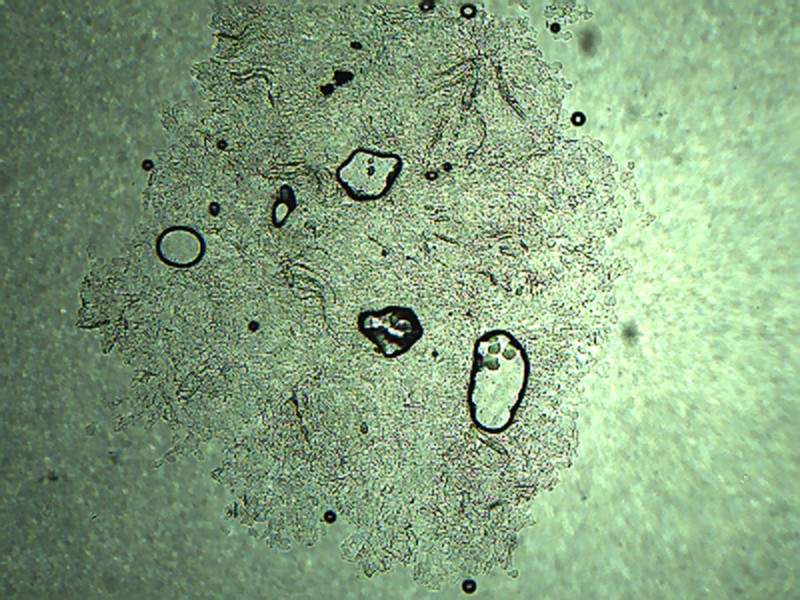

求教小孢子霉菌观察的问题